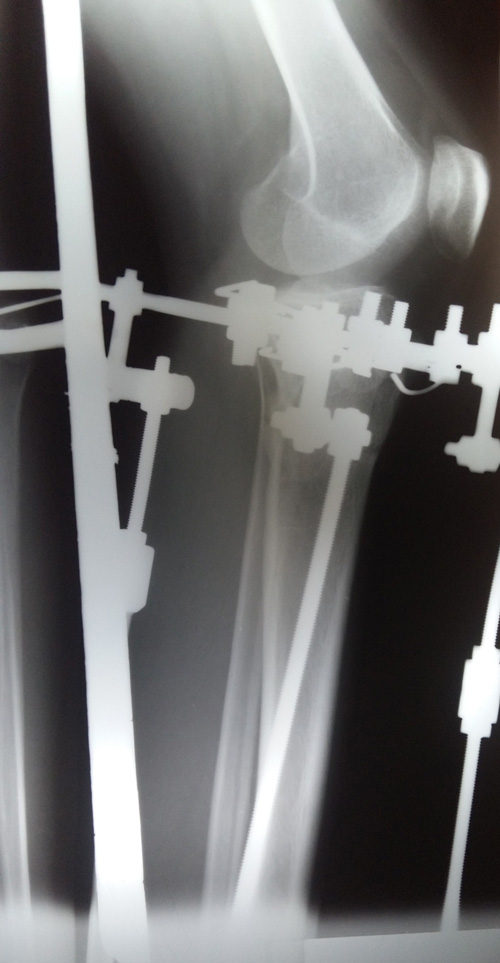

Рентген в 81 день с момента операции.

Здравствуйте, Соломея! По рентгену, у Вас всё отлично! В 90 дней возможно снятие аппаратов. Натаптывайте интенсивно ножки все эти дни, но без фанатизма(ведь когда я Вам говорю больше ходите- это значит, что при физ нагрузке быстрее разрастается костная ткань - вырабатывается, наступает сращение) лучше приехать и остаться у нас в клинике до снятия аппаратов. Один раз можно пожертвовать временем, расстоянием и средствами ради благополучия и отличного результата! Ножки мы исправляем один раз и навсегда!